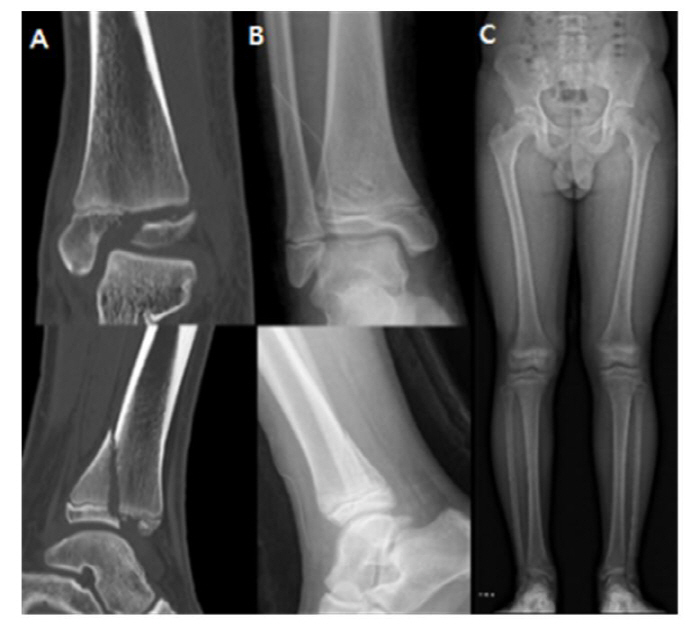

[스포츠조선 장종호 기자] 분당서울대병원 정형외과 성기혁 교수 연구팀이 소아의 발목 성장판 골절 치료에 사용하는 생체흡수성 나사와 금속 나사를 이용한 수술 결과를 비교한 연구 결과를 발표했다.

연구팀은 발목 성장판 골절로 수술을 받은 15세 이하의 환아 67명을 대상으로, 금속 나사(40명)와 생체흡수성 나사(27명)를 이용한 수술 결과를 비교했다. 그 결과, 두 군 모두에서 성장판 손상 비율, 수술 시간, 수술 후 발목 기능이 우수했으며, 수술 후 감염, 상처 등 합병증 또한 없어 유의미한 차이 없이 동등한 치료 결과를 보였다.